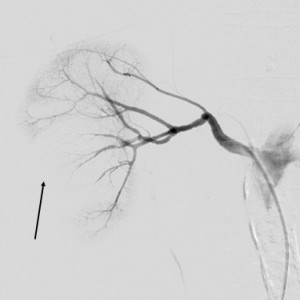

The patient was under observation on the cathlab floor during the next 60 minutes and after that the sheath was removed and hemostasis was achieved. She returned to her room but no longer then 15 minutes after she reported nausea, diaphoresis and weakness. Hypoglycemia was initially suspected but the glucotest showed a 260 mg/dl value of the serum glucose. The patient became hypotensive (systolic blood pressure 80 mm Hg) and soon after she complained of increasing pain in the right lumbar area. An ultrasound made at the bedside showed a right perirenal hematoma. The lab test indicated a dramatic decrease in the hemoglobin level, from 13 mg/dl to 8.0 mg /dl. The patient was practically in hemorrhagic shock. The decision was to transfer immediately the patient to the cathlab for an angiographic control. A new puncture of the right femoral artery was made, because the initial suspicion was an iliac rupture or perforation in the stent area, due to the extensive calcification of the arterial wall. The first injection of contrast media through the sheath showed that there was no problem with the stent. After that a global injection into the abdominal aorta, at the renal arteries level, was made, and a small effraction in the right renal parenchyma was observed (Figure 3). Selective intubation of the right renal artery was made with a JR 4.0 diagnostic catheter and that confirmed the source of bleeding in the right posterior segmental artery (Figure 4). Careful superselective intubation of this branch was performed (Figure 5), and small particles of gelatin sponge (Gelaspon) mixed with contrast media were delivered through the catheter. The embolization7 was successful in stopping the bleeding (Figure 6) but since there was about 20% of the renal parenchyma without vascularization and the patient still had important pain in the lumbar area, the decision was to transfer her to the urology department. A CT-scan (Figure 7) indicated a large subcapsular and retroperitoneal hematoma and also the presence of the contrast media in the urinary tract, an indication that the renal function was still preserved. In accordance with these findings, a renal lobectomy (partial nephrectomy) was performed, along with the evacuation of the hematoma. There was a parenchymal sparing intervention that preserved almost the entire kidney. The outcome was complicated by a pneumothorax after a central venous catheter insertion and by a right femoral hematoma following the two arterial punctures. However, after 14 days the patient was discharged in pretty good condition. One year later she has no claudication, the pulse in the right femoral artery is very good and the serum creatinine is normal.

Figure 6. Result after embolisation: the bleeding has been stopped but about 20% of the renal parenchyma is not vascularised.